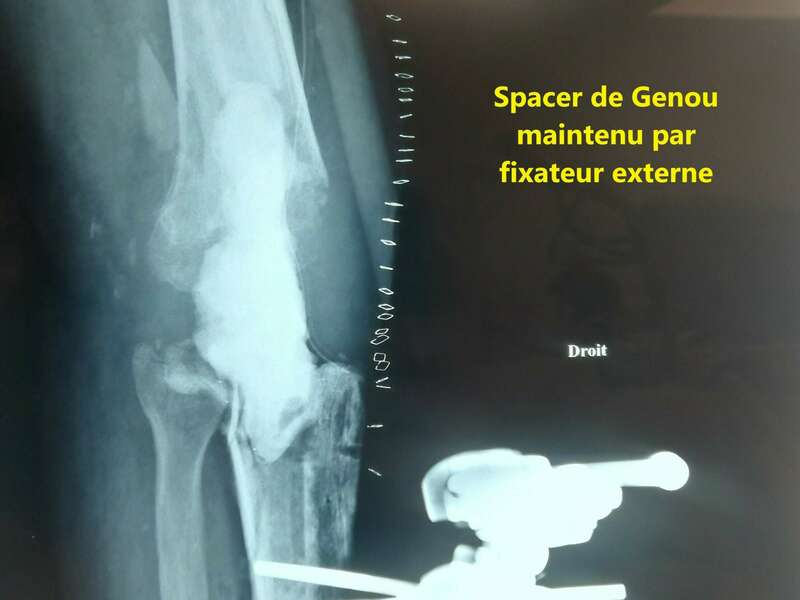

En cas d’infection tardive, la prise en charge varie d’une région à l’autre. Nous optons pour la solution en deux temps. Le premier temps correspond au retrait de l’ensemble des implants, à la réalisation de prélèvements microbiologiques, et à la mise en place d’un Spacer au ciment aux antibiotiques. Selon les constatations per-opératoires, le chirurgien décidera ou non d’introduire une antibiothérapie probabiliste avant d’avoir les résultats bactériologiques.

Un suivi clinique régulier permettra de vérifier l’amélioration clinique, la normalisation du bilan sanguin, et la tolérance aux antibiotiques. Le second temps aura lieu 6 semaines à 3 mois après le premier temps si le patient ne présente plus de symptômes et que son bilan biologique est normal. Le chirurgien reposera alors une nouvelle prothèse. L’antibiothérapie sera poursuivie après le geste chirurgical.